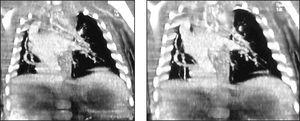

La evolución del niño es favorable en las siguientes horas, cediendo progresivamente la dificultad respiratoria, y manteniendo buenas saturaciones sin necesidad de oxígeno suplementario a partir del primer día de vida. Con este cuadro clínico se realiza tomografía computarizada (TC) torácica con contraste (figs. 2 y 3) para completar el estudio.

Figura 2.TC torácica con contraste.

Figura 3.TC torácica con contraste.